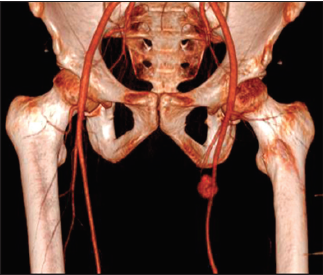

Objetivo: El objetivo del trabajo es presentar una opción terapéutica adecuada para los pseudoaneurismas de la femoral profunda secundarios a trauma penetrante, así como realizar una revisión de la literatura sobre el manejo en estas patologías. Caso clínico: Paciente masculino de 21 años quien 5 meses previos a su valoración sufre una herida por arma punzocortante en el muslo izquierdo, desarrollando aumento de volumen el sitio de la lesión, dolor y limitación al movimiento. Se diagnostica un pseudoaneurisma de la arteria femoral profunda de 2,3 cm x 2,1 cm x 2,7 cm y un hematoma adyacente de 13,5 cm x 12,6 cm x 23 cm. Se realiza exclusión del pseudoaneurisma mediante cirugía endovascular con coils, posteriormente se evacúa el hematoma adyacente. Resultados: El paciente egresa al tercer día posoperatorio con mejoría de la sintomatología, antibioticoterapia y analgesia. Discusión y Conclusión: En el caso presentado la exclusión del pseudoaneurisma mediante coils facilitó el control de éste y la evacuación del hematoma adyacente, disminuyendo el riesgo de sangrado. Por lo que consideramos adecuada esta conducta terapéutica en pseudoaneurismas de la femoral profunda